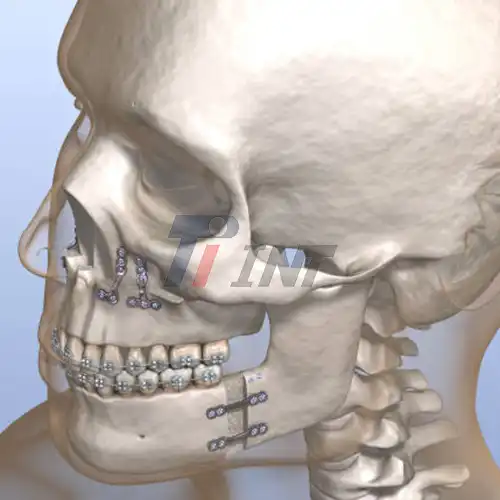

2025-12-17 08:34:05Minimizing Complications in Mandibular Fracture Repair with Titanium Plate Fixation

2025-12-18 08:33:05Post-Surgery Recovery with Titanium Plate Fixation for Mandibular Fractures

2025-06-18 10:40:11Titanium Plates for Facial Fractures: A Trusted Solution for Orthopedic Surgeons